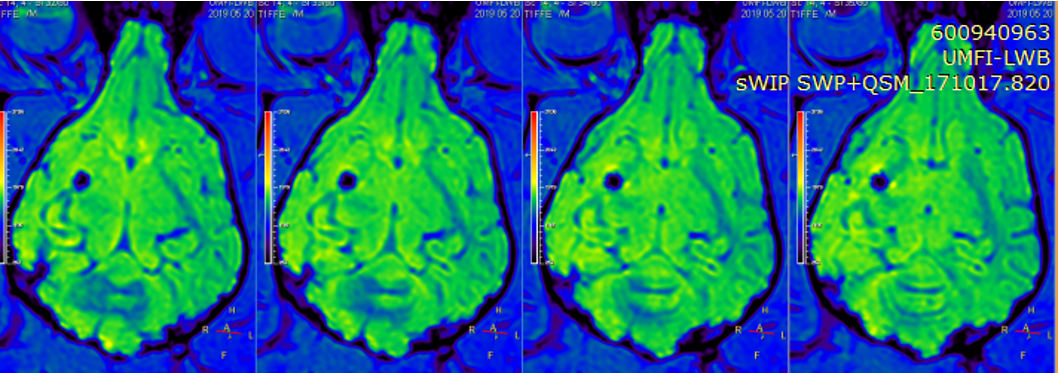

中心的研究团队包括多名医学影像领域的著名科学家和青年骨干,以医学成像和临床应用研究为核心,推动其在中国的发展,并在科技创新、产业结合方面提供多学科全球化的科研、教学和临床服务。影像中心拥有两台先进的3T全身磁共振成像系统(Philips Ingenia CX 3.0T和Siemens Prisma 3.0T),一台超高场5T全身磁共振成像系统(联影 Jupiter 5.0T),多套超声成像系统(含一台ICONEUS 脑功能超声成像系统),以及配套的成像技术、软硬件开发平台、图像数据处理工具和临床图像处理软件。中心的专业运行和技术支持团队以磁共振平台为核心,面向用户提供优秀的基础科学研究、成像技术研发和临床医学转化服务。

影像中心自成立以来,承担了科技部、国家自然科学基金委、卫生部、北京市科委等近百项国家和省部级项目,收到各种研究经费支持达5000万余元,已发表论文600余篇,发明专利60余项,国际专利10余项,培养学生130余人,获得各种奖励30余项。影像中心已成为全球重要的医学影像尤其是磁共振技术研发中心,开发出大视野高分辨血管壁多对比度成像、三维心肌定量成像、定量血流成像、定量生理成像、无变形高分辨率弥散成像等诸多原创技术,同时这些技术被广泛地应用在多项大规模临床人群队列研究当中形成了针对心脑血管、神经变性性疾病等原创性影像学解决方案。